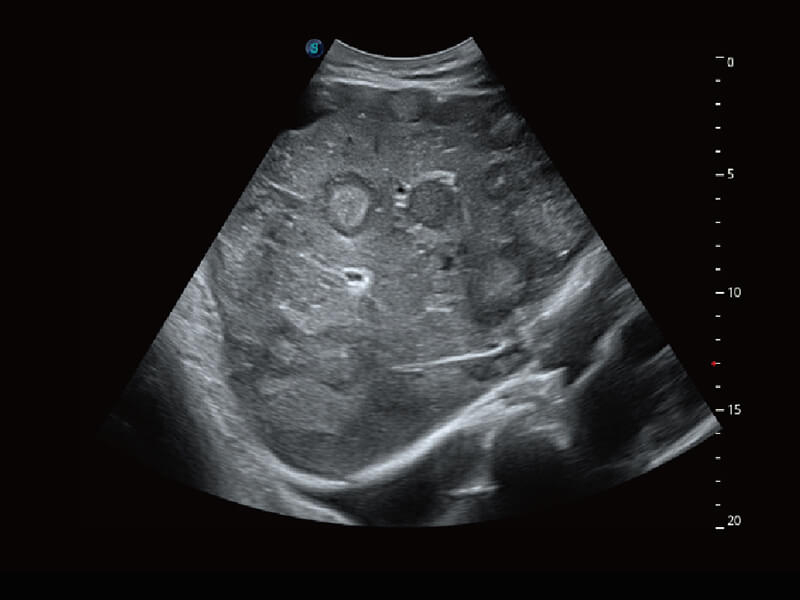

性能卓越的全新硬件架构,极大提升超声系统的运行效率和数据处理能力。相比以往超声成像系统,Wis+平台为您带来更快的响应速度和成像帧频,提升检查流畅度。

S60创新的探头工艺、高精度模数转换系统、前沿的波束重建技术,从前端信号处理每一个环节采集无损声学数据,真实还原组织原貌,再现解剖细节。